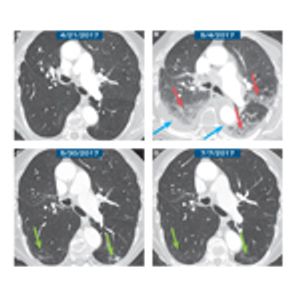

While the incidence of irAEs is relatively low, the absolute number of patients receiving immune checkpoint inhibitors is steadily increasing. Thus, it is likely that, with time, larger numbers of patients will develop irAEs, including pneumonitis.